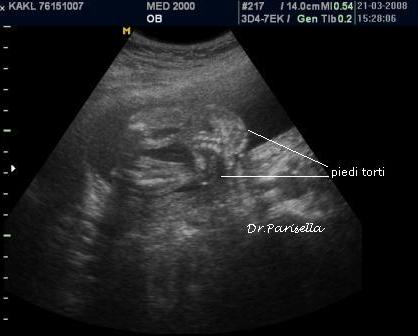

La diagnosi prenatale si basa su:

2) contratture articolari;